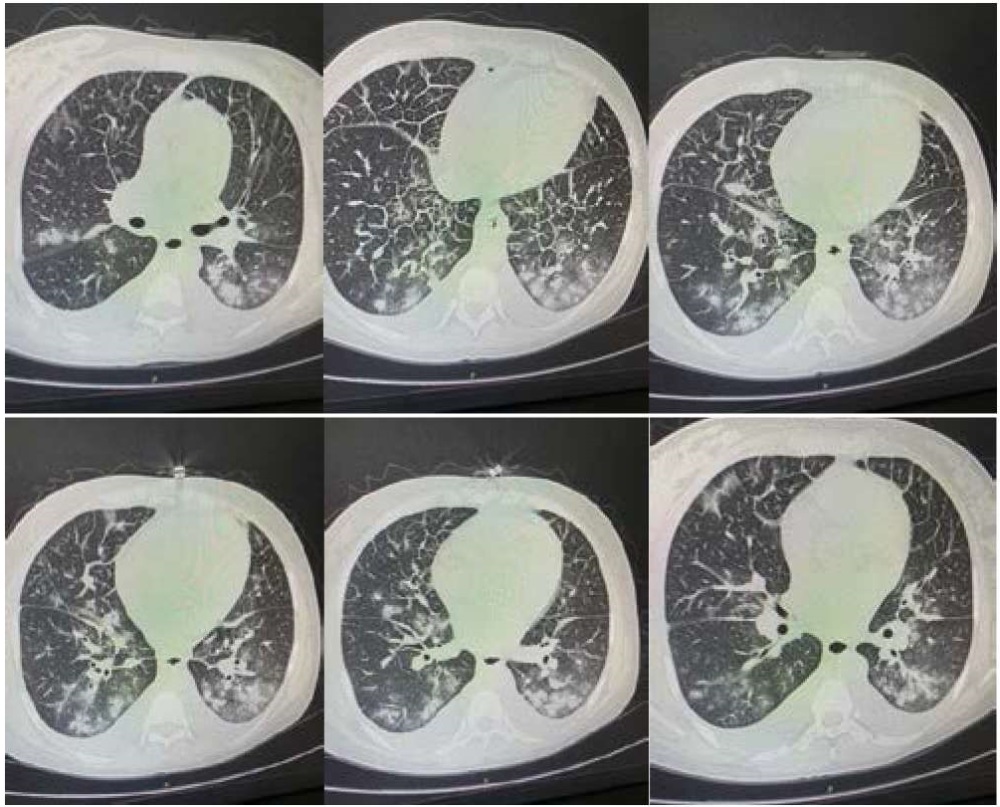

На рисунках 2–7 представлены результаты компьютерной томографии лёгких от 04.06.2021 г.

Рисунки 2–7. Результаты КТ лёгких пациентки Т. (04.06.2021)

Figure 2–7. The results of СТ scans of the lungs of a patient T. (04.06.2021)

На сканах лёгкие уменьшены в объёме за счёт наличия в обеих плевральных полостях жидкости толщиной слоя справа до 18 мм, слева до 20 мм. Полисегментарно в обоих лёгких определяются участки перибронхиальной инфильтрации. Диффузное утолщение междолькового интерстиция в обоих лёгких. В полости перикарда жидкость толщиной слоя до 9 мм. Заключение: двусторонняя полисегментарная пневмония. КТ-картина не исключает формирующегося отёка лёгких. Двусторонний гидроторакс, гидроперикард.

На рисунках 11–16 представлены результаты КТ грудной клетки (15.06.2021): наблюдается положительная динамика двусторонней полисегментарной пневмонии (вирусная, КТ 1). Малый гидроперикард.

Рисунок 11–16. Результаты КТ лёгких пациентки Т. в динамике (15.06.2021)

Figure 11–16. CТ scans of the lungs of a patient T. in dynamics (15.06.2021)